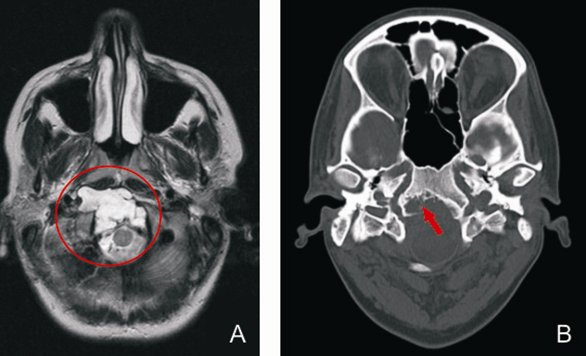

Chordome sind extrem seltene Tumore (1 / 1.000.000 Einwohner). Sie bilden sich während der Embryonalentwicklung aus der sog. Notachorda („Urwirbelsäule“). Daher treten sie an beiden Extremitäten der Wirbelsäule auf: entweder am Kopf-Hals Übergang (Kranio-zervikaler Übergang) oder am Kreuzbein (Os sacrum). Durch langsames und infiltrierendes Wachstum zeigen sie sich meist im jungen Erwachsenenalter. Typische Symptome sind Kopf-, Nacken- bzw. Kreuzschmerzen sowie neurologische Ausfälle (Doppelbilder, Schluckstörung, Lähmung bzw. Taubheit). Diagnostiziert werden sie durch CT und MRT.

Metastasen müssen durch eine Ganzkörperuntersuchung (sog. Staging) ausgeschlossen werden. Die Behandlung der Kranio-zervikalen Chordome ist komplex und sollte Zentren mit großer oto-/ neurochirurgischer, strahlentherapeutischer und onkologischer Erfahrung vorbehalten bleiben. Die Chancen sind am besten sind, wenn der Tumor bei der Erstoperation möglichst komplett aber funktionserhaltend entfernt wird. Im Anschluss muss eine hochenergetische Strahlentherapie (Protonen oder Carbon-Ionen) stattfinden.  Die Behandlungsstrategie wird auf der Grundlage der modernsten wissenschaftlichen Erkenntnisse in einer interdisziplinären Tumorkonferenz definiert. Chordomoperationen an der Schädelbasis erfolgen im UKD immer in einem spezialisierten Team aus Neuro-und HNO-Chirurgen. Oft ist ein transnasales Vorgehen mit dem Endoskop möglich. Bei Rezidiven oder Beteiligung der Halswirbelsäule wird ein Mikroskop eingesetzt. Auch der kombinierte Einsatz beider Verfahren kann im Einzelfall erfolgen. Wenn es durch den Tumor oder durch die OP zu einer Instabilität zwischen Kopf und Halswirbelsäule kommt, kann eine Stabilisierungsoperation nötig sein.